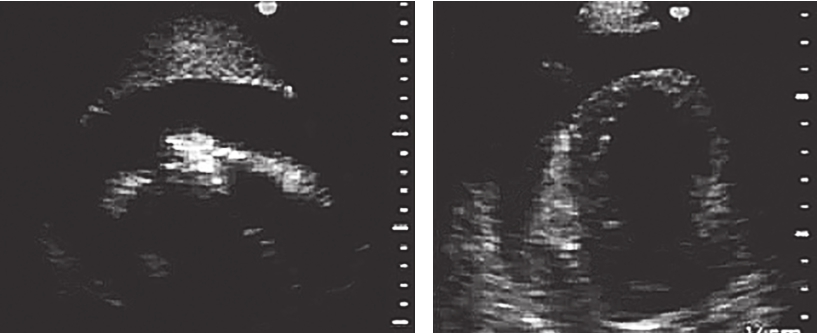

4.超声心动图(2017年4月6日)

静息状态下可见左室前间壁心尖段、室间隔及左室前壁心尖段室壁变薄(约4mm),回声偏低,运动明显减弱;心包检查可见中-大量液性暗区包绕心脏,心脏呈“摆动征”;右房、右室受压变小(图3)。

图3入院时超声心动图

左室前壁右室梗死的超声心动图特征为于心尖四腔心切面显示室间隔心尖段运动异常,并延续至右室心尖部,可累及右室游离壁近心尖区。右室心尖部运动异常区呈正三角形,宽底在右室心尖1/3处,梗死顶部指向心底部。右室游离壁破裂的超声心动图表现为:①右室游离壁破口对应的心包腔内可见不同程度的液性暗区;心包腔内液性暗区迅速增宽为心脏压塞的特征性图像改变,彩色多普勒于相应切面可见心包腔内液性暗区中红或蓝色血流束,由穿孔处至心包腔;②穿孔的室壁可于相应心腔切面上呈现心室壁回声中断;穿孔部位的心肌较薄且运动失常;③由于心包腔内压力增高,心室收缩力减弱,穿孔处的血流速度多较低。心肌破裂处无论位于前壁或下壁,均为纵行裂口,表层裂口较大,里层较小,常常形成迂曲不整的孔道。由于右室解剖形态的特殊性,并受常规心脏超声切面观察角度的局限,本例患者多次超声检查均未能明确破口位置,是诊断困难的原因之一。心包积液临床症状的发生主要是由于大量心包积液压迫心脏和周围器官及组织所引起,取决于心包腔内的液体量、液体蓄积增加的速度和心包的特征。当心包腔内液体量缓慢增加时,有一定弹性的心包被扩展以接受所增加的液体量,而心包腔内压力几乎不变。在此情况下,心包腔内液体蓄积可达2000ml而不引起心包腔内压力升高。相反,若心包腔内液体量增加迅速,即使200ml也可引起心包腔内压力急剧升高,使心脏受压而产生血流动力学变化。本例患者第一次心包穿刺引流量为560ml,此后间隔2~3个月定期复查并先后行4次心包穿刺,引流量分别为1370ml、590ml、920ml、970ml,性质相同,均为血性心包积液。曾反复行肿瘤、结核及其他病原学相关检查,未见阳性发现。考虑存在超声无法探明的心肌梗死后心肌微小破裂,保守治疗未能正常愈合,致血液持续渗出心包腔,为了证实这一推论,又对患者进行了心肌声学造影及增强磁共振成像,结果示心肌声学造影无异常发现,增强磁共振成像可见存在心包腔至心室方向的湍流信号,提示心肌微小裂孔的可能。因右室压力显著低于左室,渗液速度缓慢,故未引起急性心脏压塞症状,是临床诊断的干扰因素,也是患者得以幸存的原因。